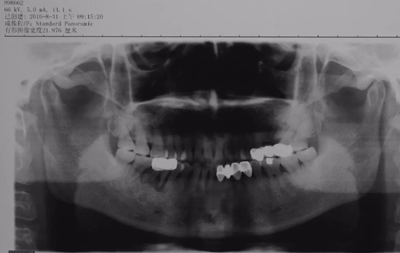

3、術(shù)前全景片

46牙烤瓷冠修復(fù),根折伴大范圍骨吸收。(攝于2016年8月31日)